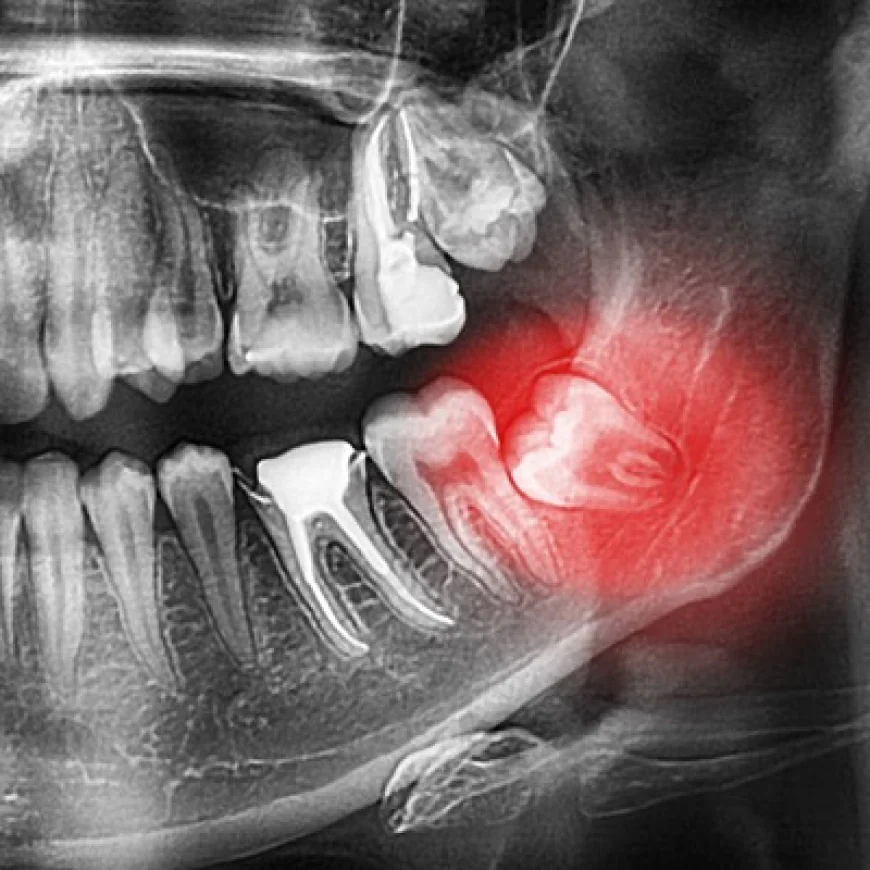

A Dental Panoramic X-Ray in Dubai provides a comprehensive, wide-view image of the entire mouth, including teeth, jaws, and surrounding structures. It helps dentists diagnose issues like impacted teeth, jaw disorders, and bone abnormalities quickly and painlessly, making it a vital tool for effective dental care and treatment planning.

A dental panoramic X-ray is a specialized two-dimensional radiographic image that captures a broad view of the entire mouth in a single image. Unlike traditional intraoral X-rays that focus on a small area, panoramic X-rays provide an overview of:

This comprehensive image gives dentists crucial information that helps in accurate diagnosis and treatment planning, particularly for dental implants.

The panoramic image shows important anatomical landmarks such as the mandibular nerve canal and maxillary sinuses. Avoiding these structures during implant surgery is crucial to prevent complications like nerve damage or sinus perforation.

For patients with remaining teeth, the panoramic X-ray helps evaluate spacing and alignment, ensuring the implant will fit properly without affecting adjacent teeth.

Panoramic imaging can reveal infections, cysts, or tumors that may need treatment before implant placement, ensuring the site is healthy.